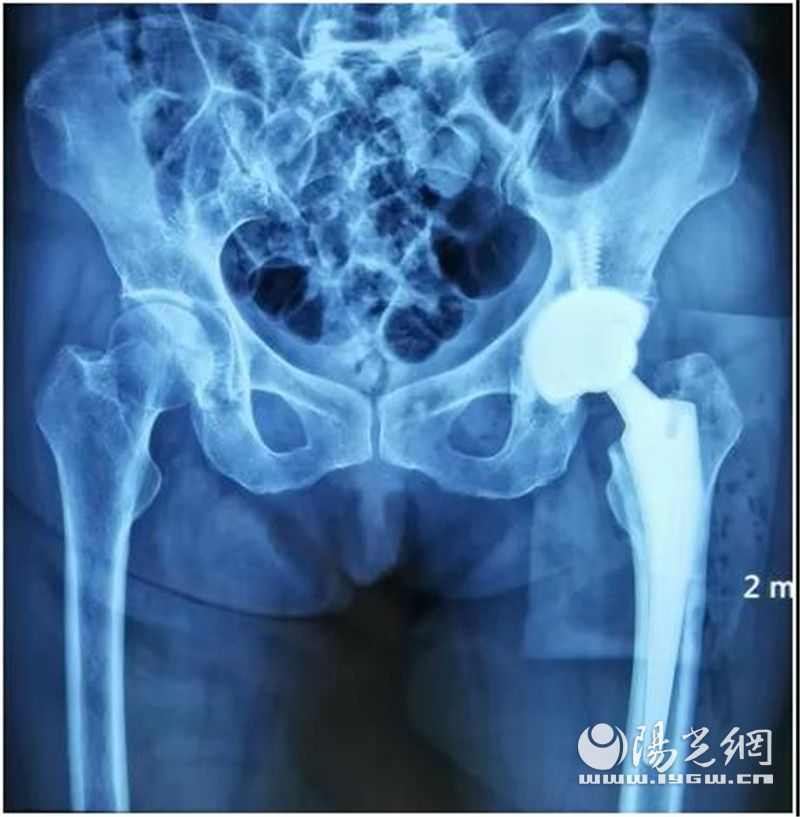

前段时间,李阿姨摔伤致左髋部疼痛伴活动受限,在家中走几步路都感觉困难,生活不能自理。不堪疼痛折磨的她,最终被家人送到西安国际医学中心医院北院区关节一科。经拍片检查及详细查体后诊断为:左侧股骨颈骨折(头下型)。

著名骨科专家朱庆生教授领衔的团队经过术前缜密分析,同患者和家属进行了充分的沟通后,最终为李阿姨实施了全髋关节置换术。术后第二天,李阿姨就能完成坐立、下蹲和自由行走等动作。

从术后复查X片看到:李阿姨髋关节假体位置良好、固定牢靠,双下肢恢复等长,第二日行走姿态及感受非常好,同时还能完成坐立、下蹲等动作,也就不足为奇了!